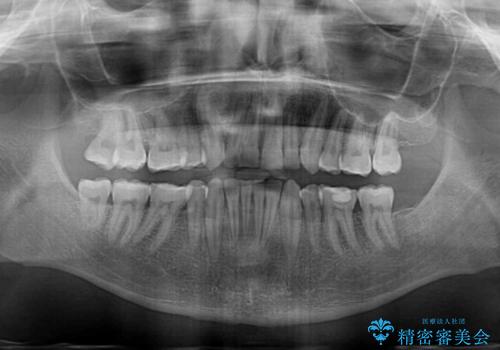

- 上下前歯の叢生を気にして来院された患者様です。

抜歯矯正をした後戻りということで、歯列不正はそれほど大きくなかったため、インビザライン・ライトを用いて矯正治療を行うこととしました。

前歯のデコボコが残っており、シミュレーション通りに動いていない部分がありましたが、再矯正であることやご本人の満足いくところまでデコボコが改善されたとのことで、治療を終了することとしました。